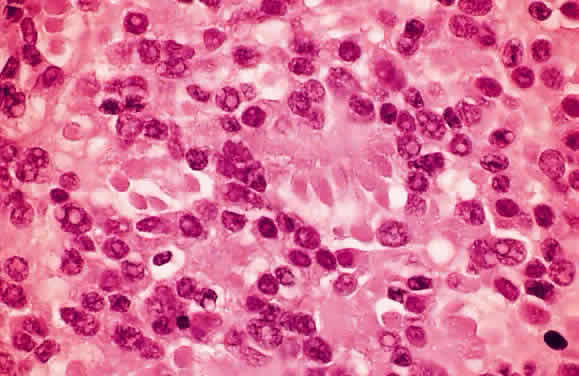

HISTOLOGY AND ULTRASTRUCTURE